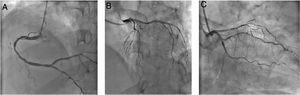

Using PPE for aerosol-generating procedures, emergent angiography performed 13 hours after symptom onset showed a good result of the previous angioplasty and non-obstructive coronary artery disease (Figure 3).

Emergent coronary angiography. (A) Right coronary artery with moderate disease in mid segment and mild disease in distal segment; (B and C) left main coronary artery with no significant lesions; left anterior descending artery with diffuse disease; left circumflex artery with mild disease and stent in mid segment without restenosis.